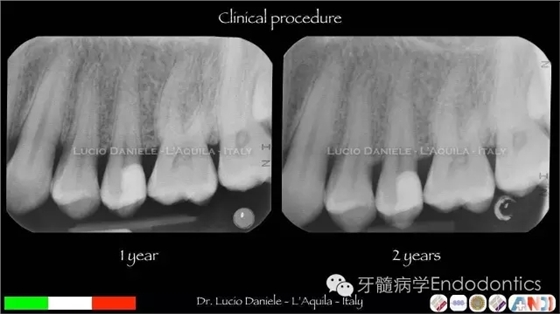

圖26.術后6個月隨訪